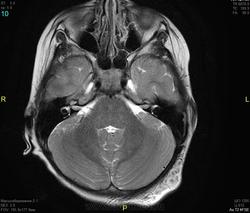

Уважаемые коллеги! Прошу консультативной помощи. Про пациента известно: девочка (7 лет), в анамнезе 2,5 года назад травма головы. Не диагностировалась. Периодически жалобы на болезненность при пальпации затылочной области(((((

Напоминает сосудистую структуру.Может, какая-нибудь лимфангиома?Видела на передней поверхности шеи, на задней - нет.

как будто связь с ликвором имеется.  Дополнил бы венографией, и FatSat"ом ну и контрастом, конечно.

Сегодня в ходе разговора с мамой девочки, выяснилось, что и у мамы есть подобное "образование". С ее слов, несколько лет назад ей делали пункцию для исключения онкологии. Результат пункции: содержится нервная ткань и лимфоциты ( опять же никаких документов я не видела). То есть можно говорить о наследственном характере.

Нейрофиброма вполне может быть. Плексиформная. Проверить на нейрофиброматоз. Я видел такой же структуры и локализации. Пятен на коже нет? Вообще на теле? И нет ли чего похожего в позадиглоточном пространстве?

есть похожее образование в позадиглоточном пространстве)

многоузловое образование  исходящее из задней части предпозвоночного пространства с переходом на подкожную жировую клетчатку головы!шваннома ,нейрофиброма и их злокачественные аналоги